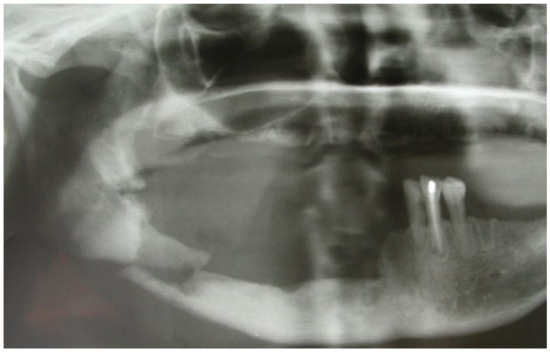

3.1. Clinical Case 1

3.2. Clinical Case 2

3.3. Clinical Case 3

3.4. Clinical Case 4

3.5. Clinical Case 5

3.6. Clinical Case 6